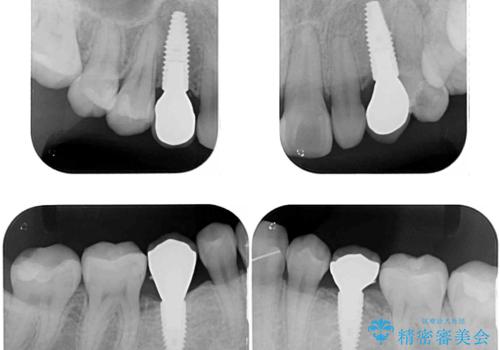

欠損と残存乳歯 矯正治療とインプラント治療

- 残存した乳歯や歯の欠損、歯並びを気にして来院された患者様です。

乳歯を残した状態は予後がよくないこと、矯正治療と補綴治療を総合的に進めていきたいとのことで、インビザラインによる矯正治療とインプラント補綴治療を並行して進めていくこととしました。

当院は矯正治療もインプラント補綴治療も、同一の歯科医師が担当するため、矯正治療を行いながら、最適なタイミングでインプラント補綴治療を行うことが可能です。